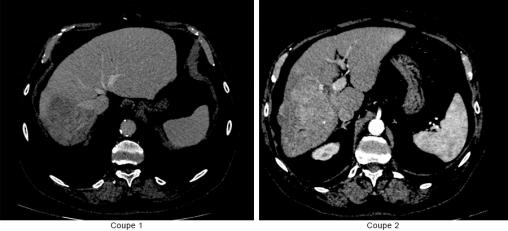

CHSD – PACS, La Revue du Praticien Nodule hépatique avec prise de contraste au temps artériel et wash out au temps portal.